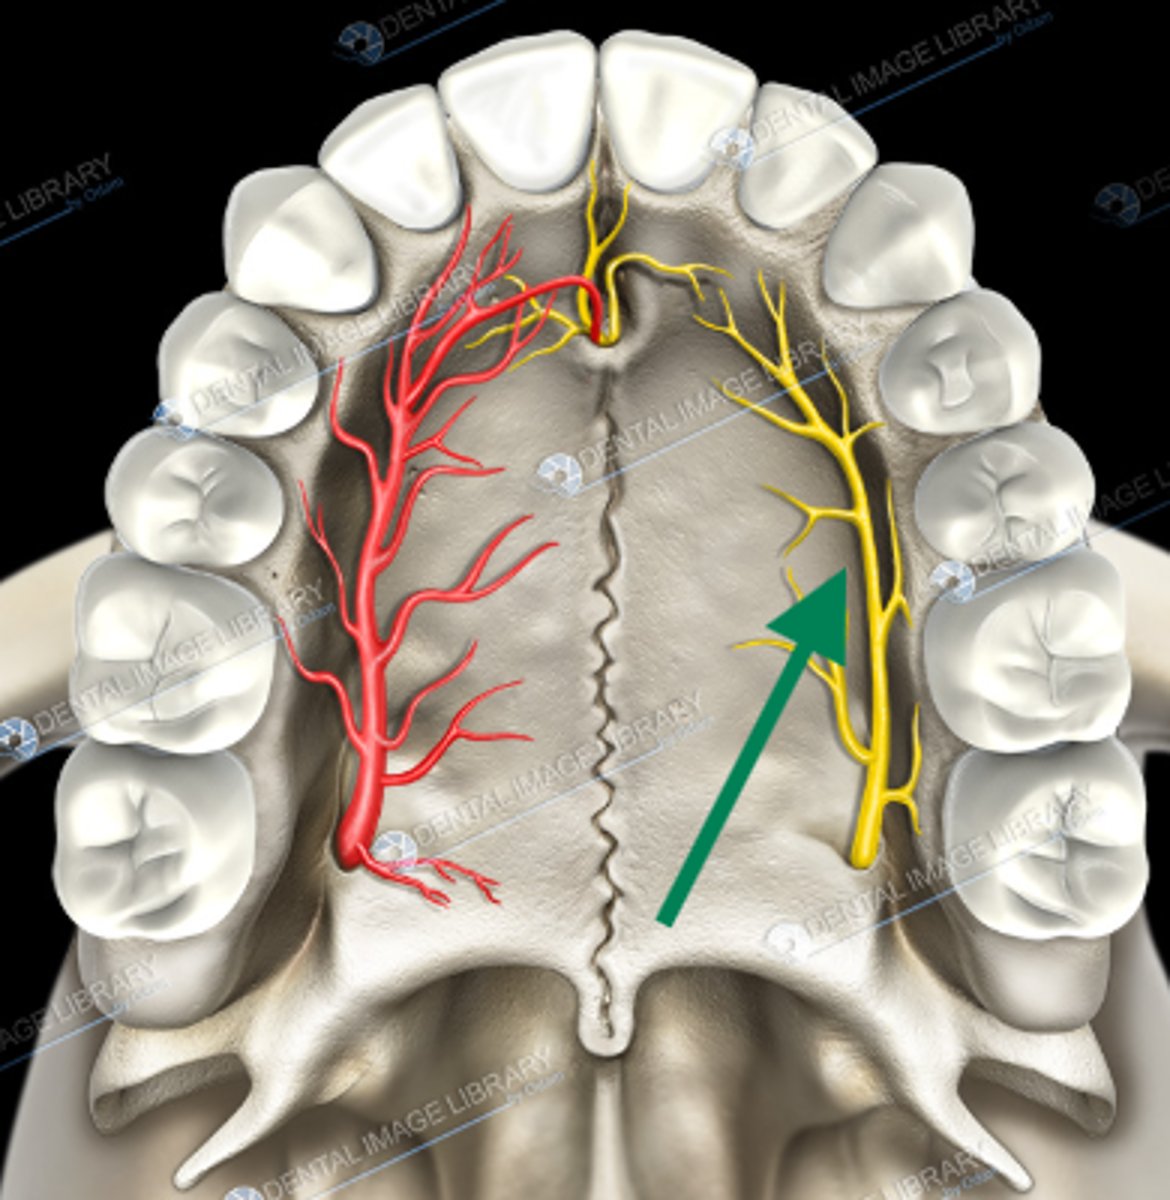

nasopalatine nerve

descending palatine artery

greater palatine nerve

greater palatine artery

greater palatine foramen

lesser palatine nerve

lesser palatine artery

greater and lesser palatine nerve

greater palatine nerve